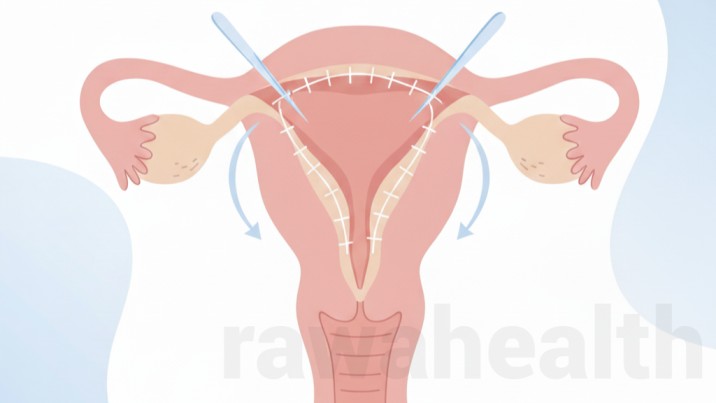

Hymenoplasty Surgery Hymenoplasty surgery is a minor gynecological procedure that repairs or reconstructs the hymen, a thin membrane located at the vaginal opening. Women choose this surgery for personal, emotional, or medical reasons. Advances in modern gynecological techniques have made hymen repair a safe, quick, and confidential procedure with minimal downtime. This detailed guide explains […]